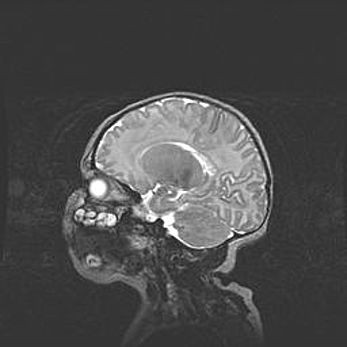

Церебральная ишемия II.

Возраст: 5 дней

Вес: 3400 г

Пол: женский

Окружность головы: 35 см

Срок гестации: 39 недель

Церебральная ишемия – это заболевание, характеризующееся недостаточностью (гипоксией) либо полным прекращением (аноксией) снабжения мозга кислородом по причине закупорки одного или нескольких сосудов. Это приводит к  что метаболическим расстройствам различной степени тяжести в тканях головного мозга, развитию коагуляционных некрозов и гибели нейронов.